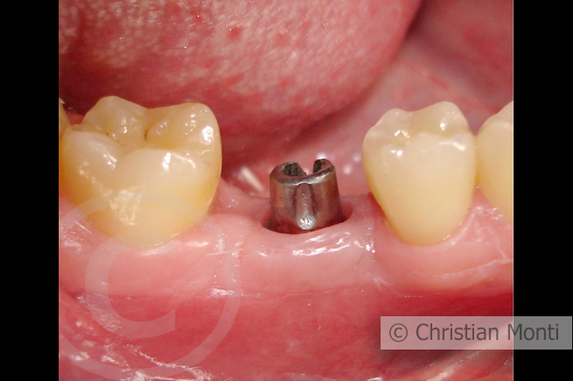

EDENTULIA SINGOLA

Impianto dilazionato in sostituzione di un molare inferiore